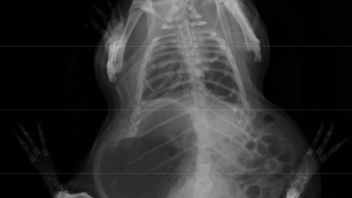

Dies zeigt an, dass etwas nicht stimmt und dass es sich hierbei um ein krankes Schweinchen handelt, auch wenn der Tierarzt nichts findet.

Da ist etwas im Argen, was es zu entdecken gibt.

Dein Tierarzt sollte so lange mit dir zusammen nach der Ursache suchen, bis sie gefunden ist.